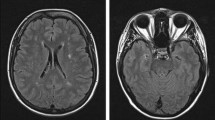

In the present study, we performed WES in 2 patients of a family with SS (Fig. 1a, subject III:2 and III:3). Clinical details of patient III:3 were previously reported [10]. Briefly, of 5 siblings 4 are affected with SS presenting livedo reticularis and a history of early onset stroke in childhood. Brain MRI from subjects III:2 and III:3 showed severe periventricular and subcortical white matter lesions and also multiple microbleeds predominantly in the white matter in sibling III:3 (Fig. 1b and Table 1). Laboratory results of sibling III:3 were negative for antiphospholipid antibodies and thrombophilia in general. No data were available on the antibody profile of the second sibling (III:2). The mother was reported to be healthy and the father, who died from a myocardial infarction at the age of 54, was reported to have had livedo reticularis but no signs of cerebrovascular disease (Fig. 1a). Exome-data analysis revealed in both siblings a large homozygous region of 9 Megabases on chr.19p13., indicating consanguinity. This region harbored only two homozygous variants shared by both siblings. First, a missense variant was detected in the KANK2 gene p.(Met278Lys), which is not present in any publicly available database. This variant was discarded since mutations in this gene have been associated with a distinct recessive disease characterized by a nephrotic syndrome and palmoplantar keratoderma with woolly hair (OMIM*614610). Second, a homozygous nonsense variant was identified in exon 14 of the NOTCH3 gene, p.(Arg735Ter) (Fig. 1b), which lies in the Epidermal Growth Factor repeat (EGFr) 19 of NOTCH3. This variant is predicted to result in a premature stop codon and elicit nonsense-mediated mRNA decay [16]. The variant is present heterozygously in 2 out of 61.000 individuals in the gnomAD database. (https://gnomad.broadinstitute.org/). The healthy mother was tested to be heterozygous for the p.(Arg735Ter) variant (Fig. 1c, II:3). No other family member was available for genetic testing either because they lived in another region of the country and were not able to transfer to the clinic for testing or were not interested in participating in the study. Based on the severity of the mutation and the known role of NOTCH3 in cerebrovascular disease, we believe that this mutation is most probably the cause of the disease in this family. To analyze whether NOTCH3 loss-of-function (lof) mutations are a more frequent cause for SS, we performed WES in 6 additional unrelated patients (Table 2). We found none of the patients to carry a rare variant (MAF < 0.01) in the NOTCH3 or in the ADA2 gene. Moreover, high coverage sequencing allowed us to also exclude copy number variations in both genes. We next hypothesized that genetic variations in genes involved in the NOTCH3 pathway might be plausible disease candidates. To explore this possibility, we made use of two microarray datasets of Notch3 KO mouse models from which RNA expression data of brain microvascular fragments (GSE55203) or brain-derived smooth muscle cells (GSE58368) were deposited. Using the GEO2R tool we searched for genes which were significantly downregulated in KO cells compared to wildtype or heterozygous cells (p value < 0.01), assuming that these genes are likely downstream in the NOTCH3 signaling pathway. We then intersected these 445 genes with the 85 genes carrying lof variants in our 6 patients. We found two patients with lof variants in putative NOTCH3 downstream genes. Patient 895 carried a heterozygous nonsense variant in the Palladin (PALLD) gene, p.(Arg287Ter) and patient 898 carried a heterozygous frameshift variant in the Angiopoietin-like 4 gene (ANGPTL4), p.(Gly313AlafsTer49). Both variants are present heterozygously in the gnomAD database (PALLD: 10/277212 alleles, ANGPTL4: 57/280350 alleles) (Fig. 2, Table 2).

Genealogical tree of the mutated family and representative brain MRI of patient III:3 a Pedigree of family 1: Unaffected family members are indicated by open symbols; affected members by closed symbols including livedo reticularis and cerebrovascular manifestations; half closed symbol (II:1) indicates partial phenotype of SS, with only livedo reticularis; diagonal bars through symbols denote deceased individuals. b Sanger-Sequence Pherograms showing the NOTCH3 variant in heterozygous form (II:3) and homozygous form (III:2, III:3). c Brain MRI from patient III:3 showing diffuse white matter hyperintensities on fluid-attenuated inversion recovery (FLAIR) images; lacunes on T1 and microbleeds on T2*-weighted images, lesions are depicted by an arrow